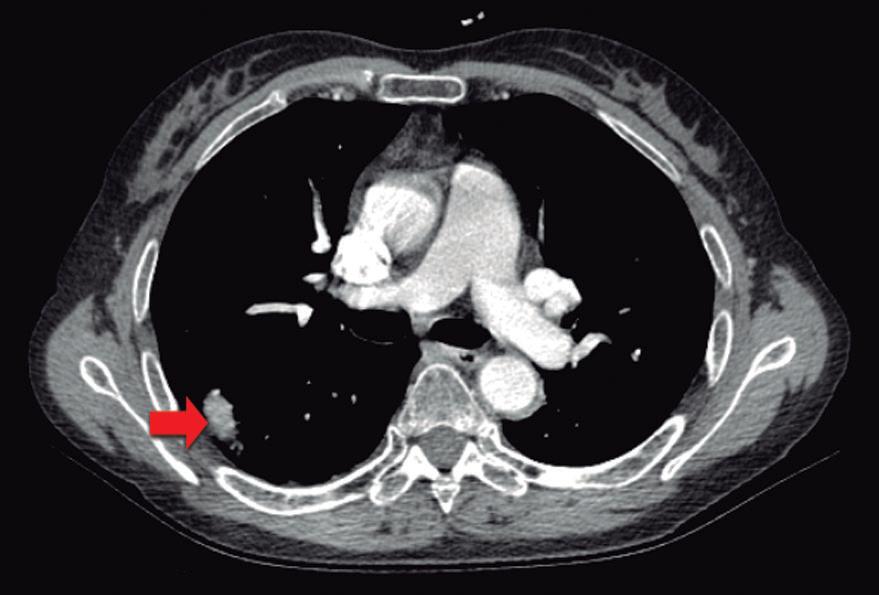

Paciente con vómitos en el periodo posoperatorio

Germán Francisco Rojas, Gabriel Adrián Mariño Camacho, Jesica Antonella Andruetto, Martín José Drago, Alejandro Moreira Grecco, Mariano Volpacchio, Esteban González Ballerga